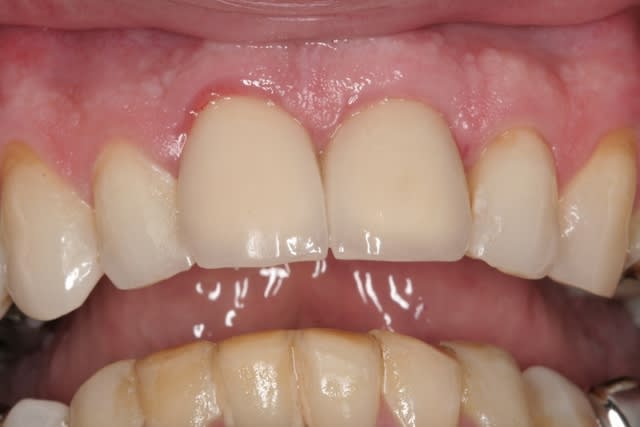

le hasard fait parfois bien les choses...patient revu ce matin pour une "bricole" sur une restauration postérieure...

il est intéressant de voir la maturation des tissus mous...et en plus VS des différences au niveau de l'hygiène, pas mal secteur 2 mais perfectible secteur 1...

ici on est à 3 mois post pose prothèses d'usage...la photo, prise un peu décalée, donne l'impression d'une différence de hauteur des collets, mais il n'en est rien (ou alors très peu...)

quand même content du résultat...;-) même si j'ai (lourdement)insisté pour que l'hygiène soit un peu mieux suivie...